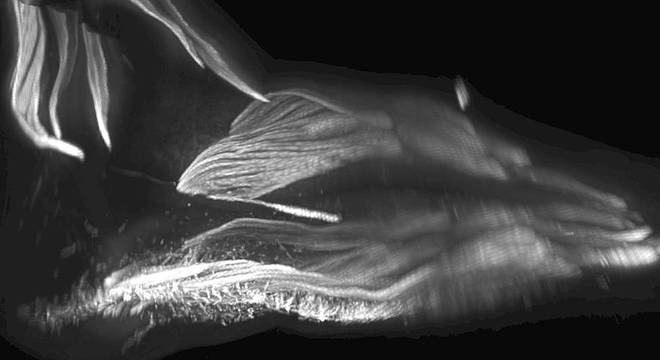

Músculos no pé de um bebê

Músculos no pé de um bebê Rui Diogo, Natalia Siomava and Yorick Gotton

Eles já estudaram os pés e como músculos extras se desenvolvem e desaparecem nessa região do corpo enquanto bebês estão no útero.

Macacos e chimpanzés também têm esses músculos e os usam para escalar árvores e manipular objetos com os pés.